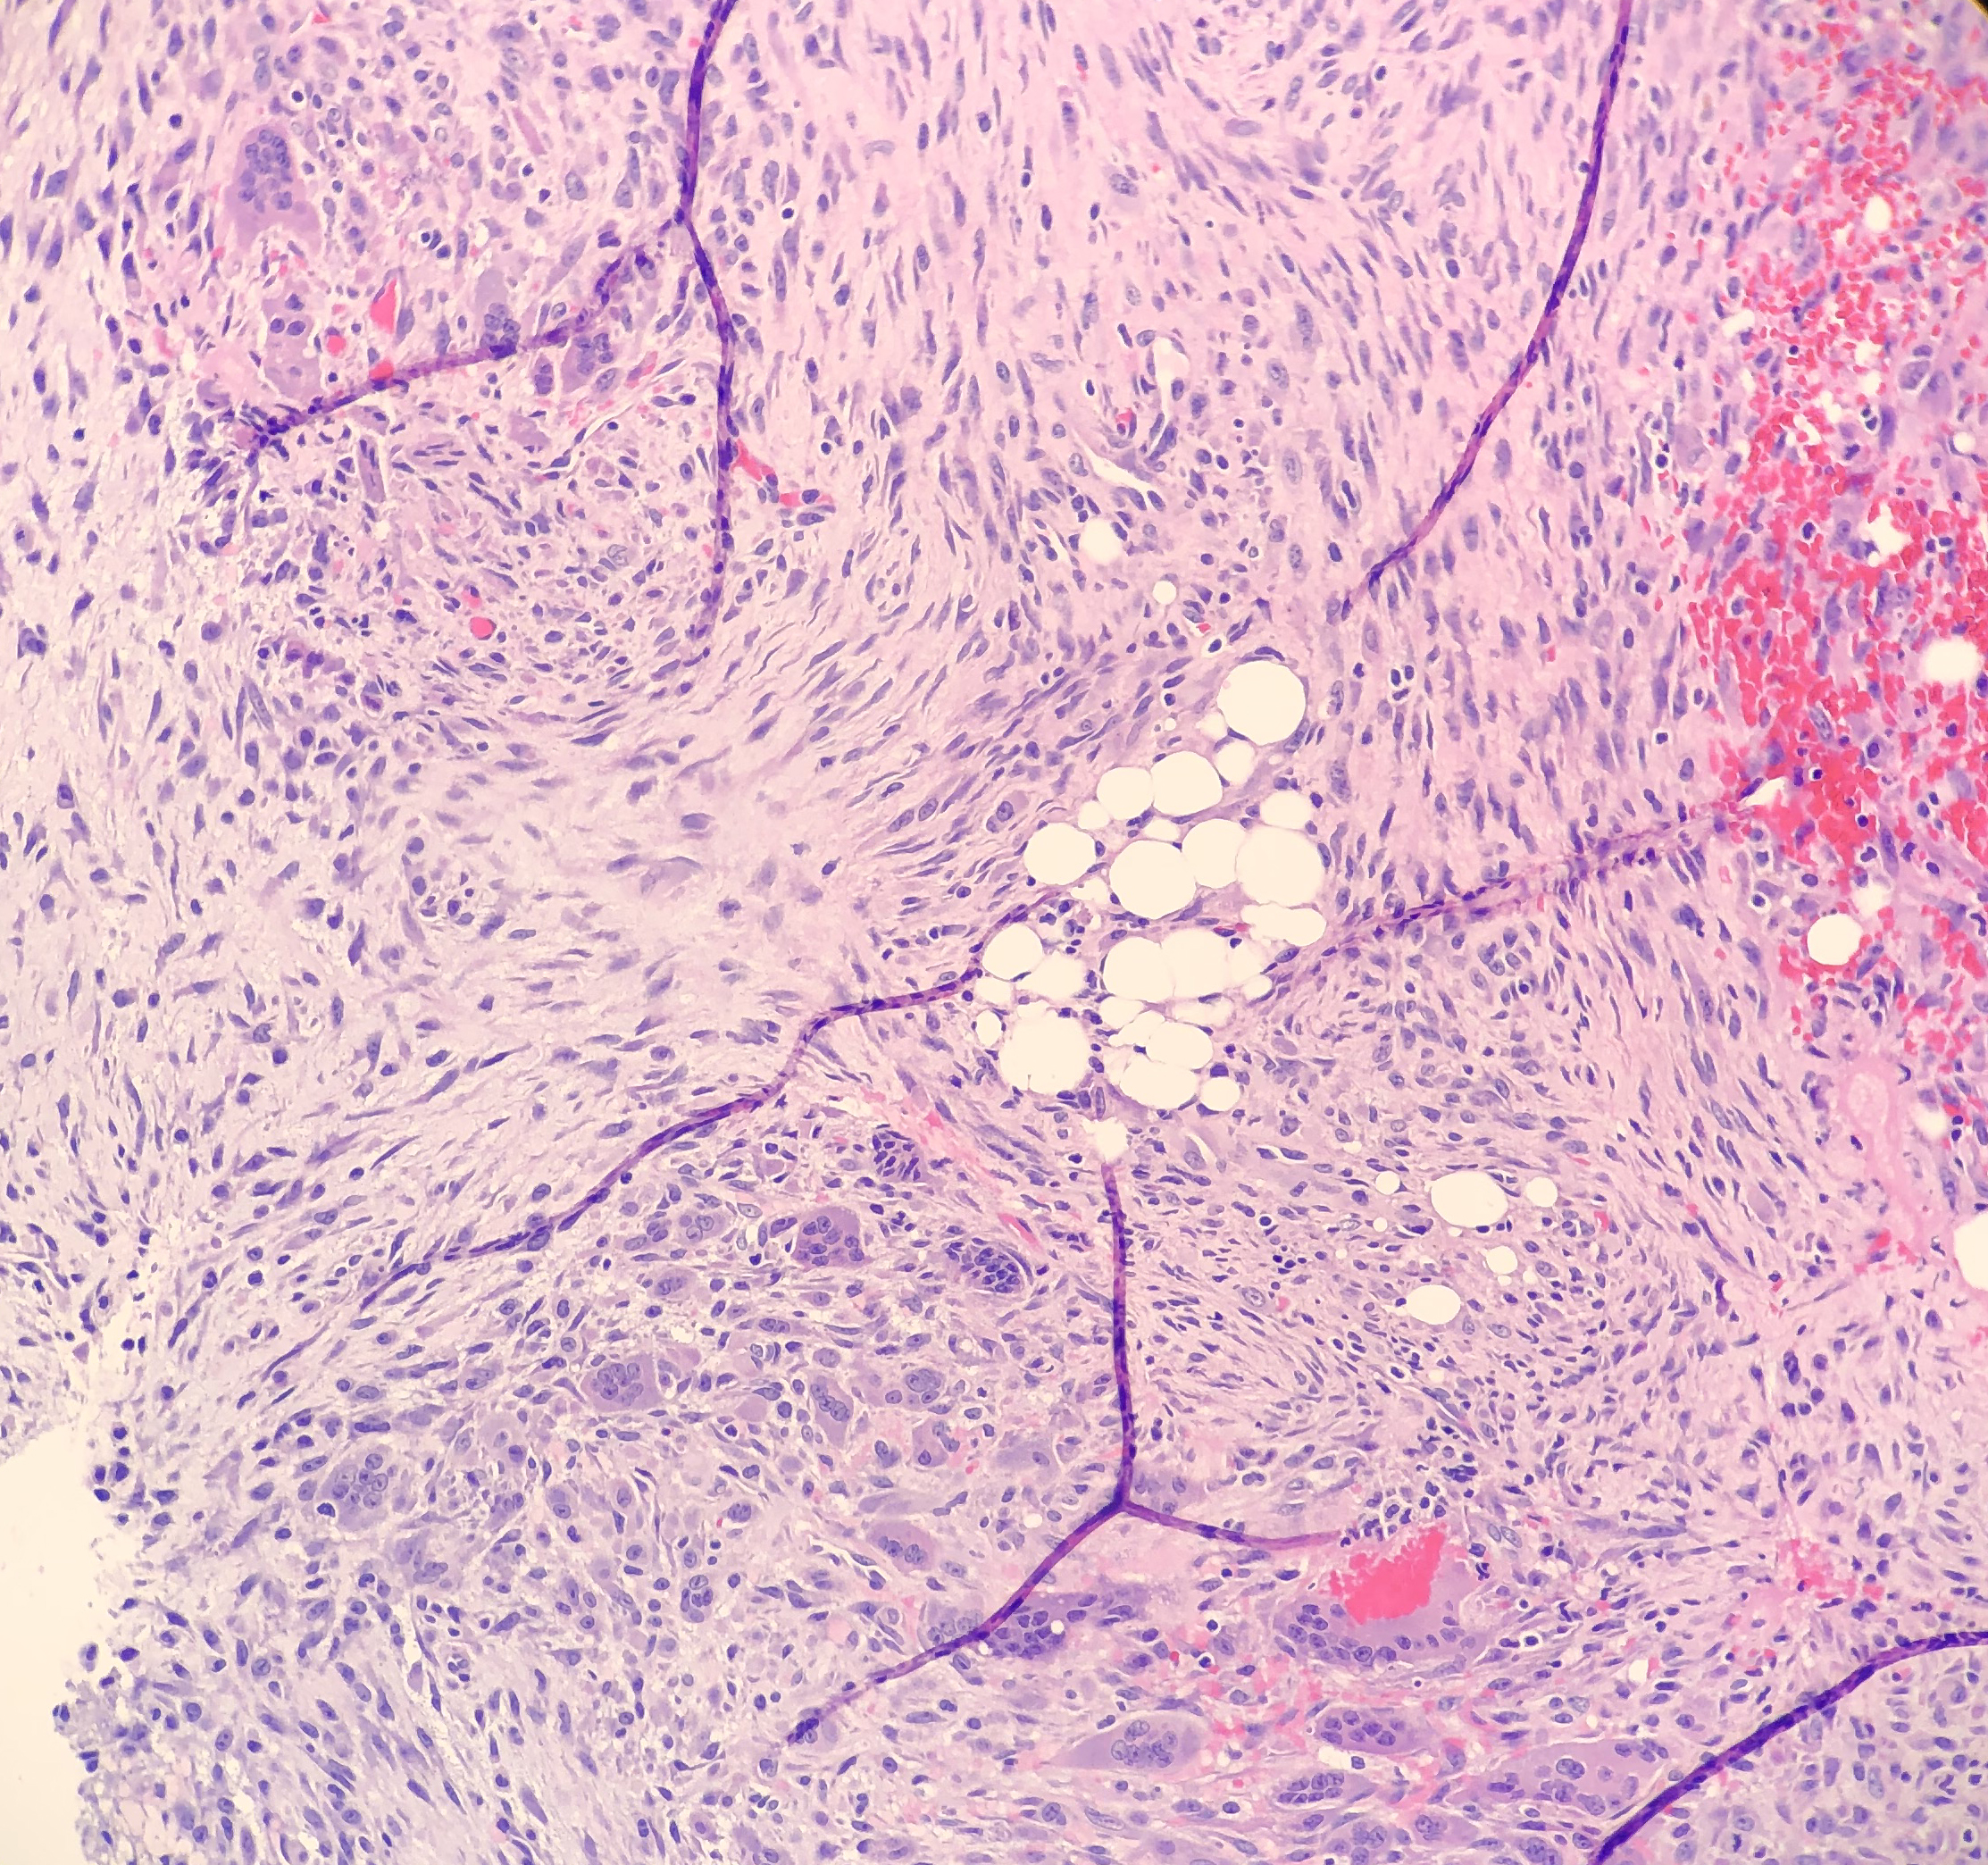

On microscopy, the biopsies demonstrate a moderately cellular proliferation of fasciculated spindle cells in a collagenous to myxoid stroma. Nuclei are predominantly oval with variably fine to granular chromatin. Many cells have moderate amounts of tapering eosinophilic cytoplasm, resembling strap cells. Inflammatory cells and osteoclast-like giant cells are admixed (Figure 3 and 4). Immunohistochemical stains demonstrate lesional spindle cells to be positive for CD31, ERG, and FLI1. AE1/AE3 and CAM5.2 highlight rare lesional spindle cells. SMA stains some stellate spindle cells, favored to represent associated myofibroblasts. Desmin, MDM2, CDK4, ALK, and S100 are negative in plump lesional cells (Figure 5 and 6). Overall, the features are consistent with pseudomyogenic hemangioendothelioma, a rare vascular tumor. Although more commonly present in soft tissue, primary bone cases have been reported. These neoplasms have some risk for local recurrence, but only rarely distant metastasis. A portion of tissue was sent to the University of Nebraska Medical Center to evaluate for a characteristic gene rearrangement (SERPINE1-FOSB) that is present in at least a subset of pseudomyogenic hemangioendotheliomas. This was negative.

Figure 3. Photomicrograph of the strap-like cells with tapering eosinophilic cytoplasm , and osteoclast-like giant cells.

Figure 4. Higher power photomicrograph demonstrating the appearance of the strap-like cells with tapering eosinophilic cytoplasmFigure 4.

Histologically, PHE demonstrates plump spindle and rhabdomyoblast-like cells with densely eosinophilic cytoplasm that grows in sheets and fascicles. The cells can be mistaken as rhabdomyoblasts because of the eosinophilic cytoplasm that pushes the nucleus to the periphery of the cell. Immunohistochemical studies are very helpful in order to determine a diagnosis of PHE. AE1/AE3, ERG, FLI-1 and CD31 are positive, whereas CD34, desmin and S100 are negative. Karyotyping has revealed a fusion of genes SERPINE1-FOSB that corresponds to the recurrent translocation t(7;19)(q22;q13). In this case, the SERPINE1-FOSBgene rearrangement was negative, but could possibly be due to a variant fusion gene.